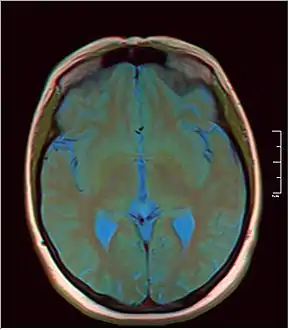

- MRI axial in false color